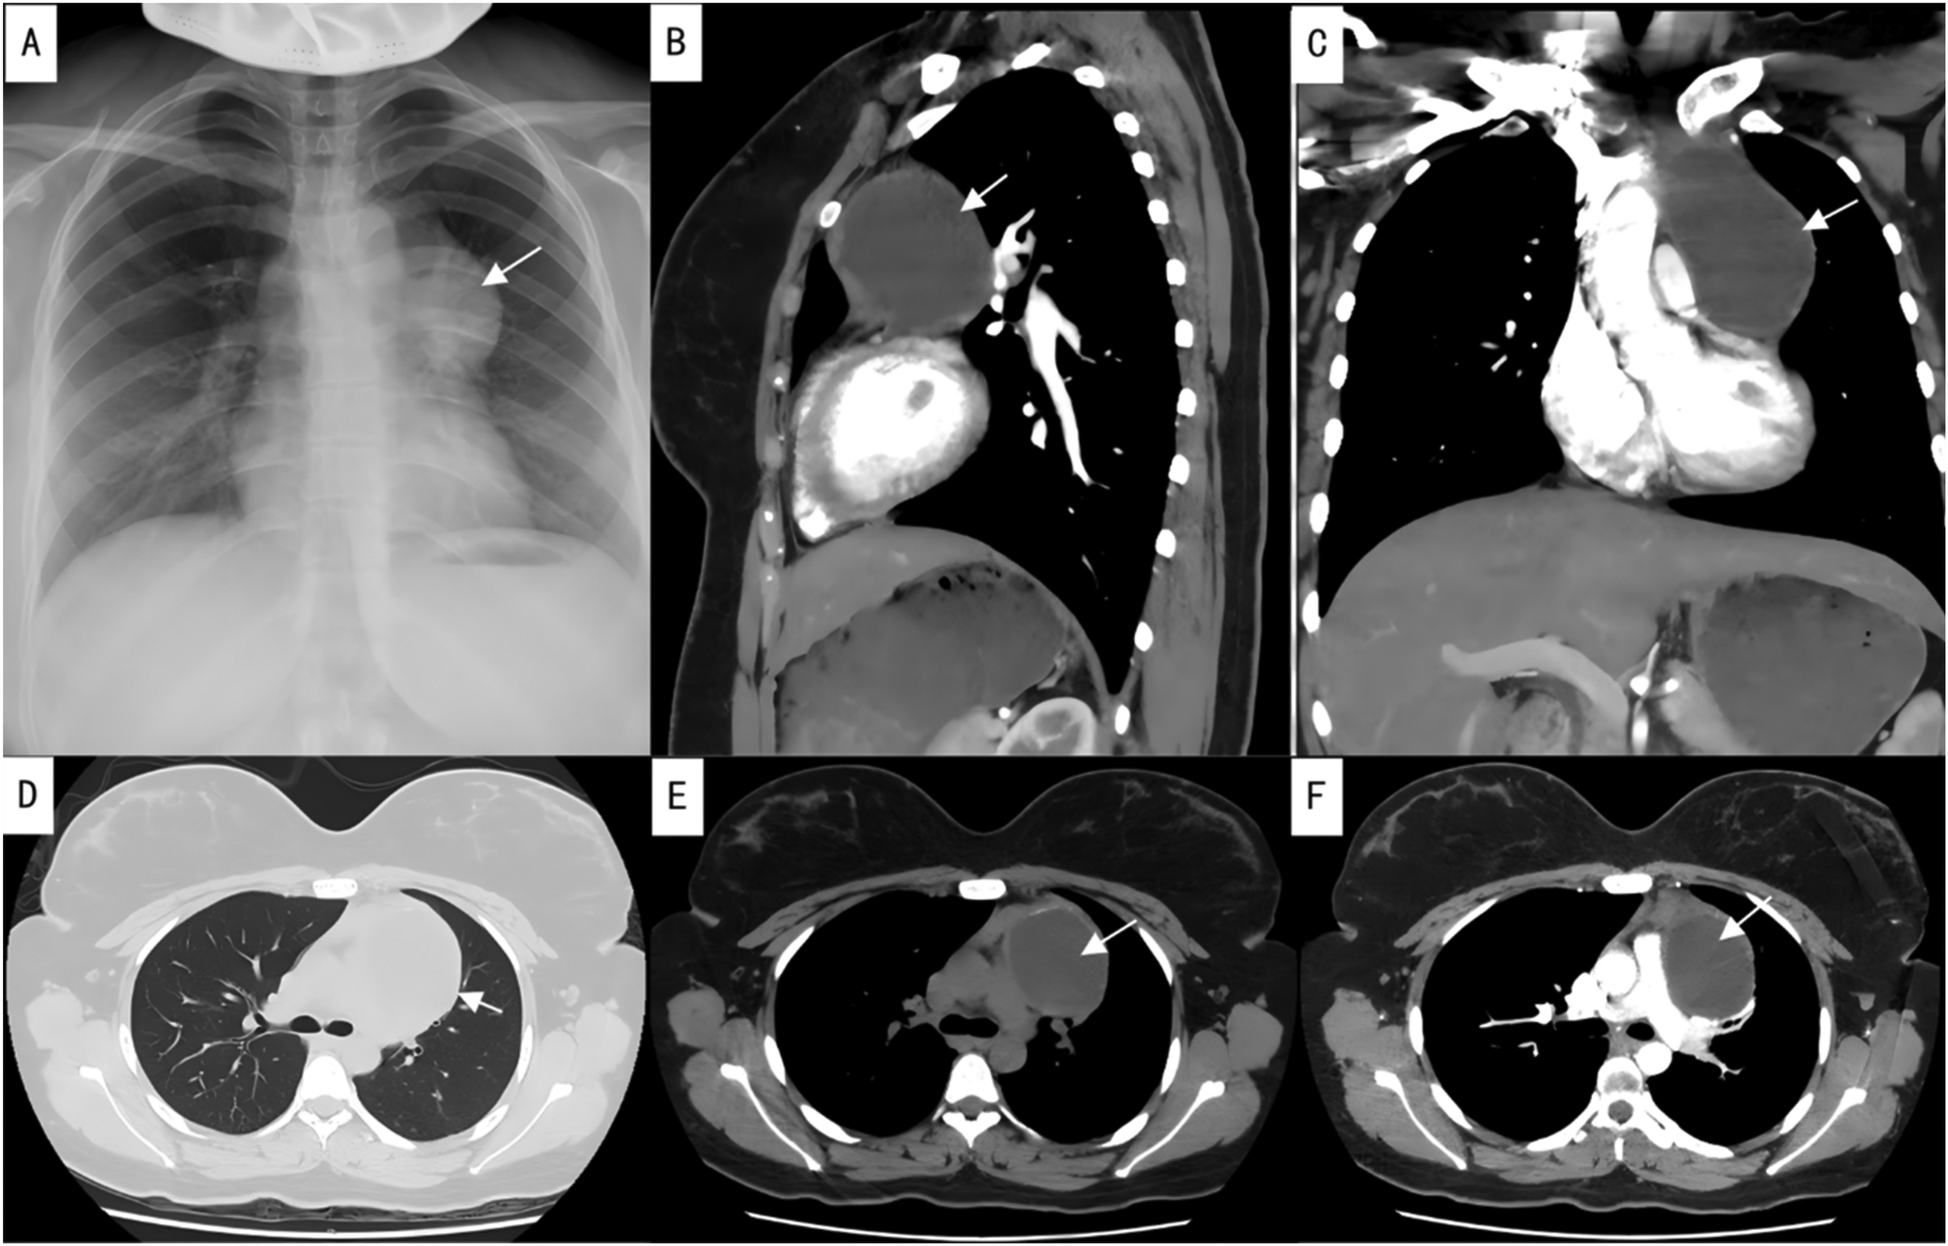

Imaging findings revealed an enlargement and unclear structure of the left hilum on routine chest x-ray (Figure 1A). Contrast-enhanced chest CT further demonstrated a cystic lesion in both the anterior mediastinum and the left side of the middle mediastinum, suggesting a benign tumor, most likely a thymic cyst, while ruling out a cystic teratoma (Figures 1B–F). Preoperative laboratory tests, including blood work, coagulation function, infectious disease screening, liver and kidney function, and an electrocardiogram, were within normal limits, with no absolute contraindications to surgery identified.

Figure 1. Preoperative imaging studies. (A) Preoperative chest x-ray; (B) sagittal view of contrast-enhanced chest CT; (C) coronal view of contrast-enhanced chest CT; (D) lung window of plain chest CT; (E) mediastinal window of plain chest CT; (F) axial view of contrast-enhanced chest CT. The arrows indicate the location of the lesion.